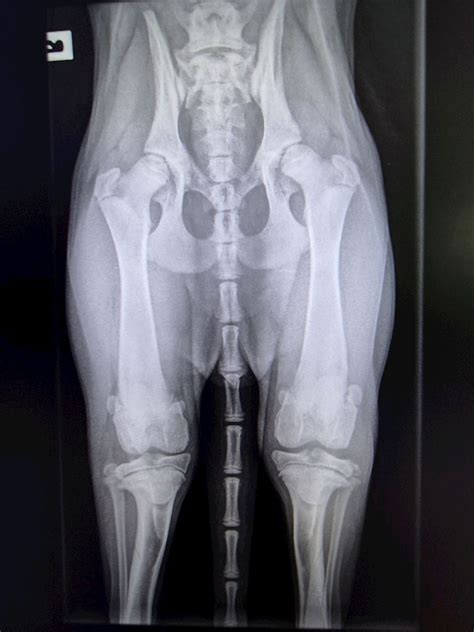

Pennhip

Pennhip. There are any references about Pennhip in here. you can look below.